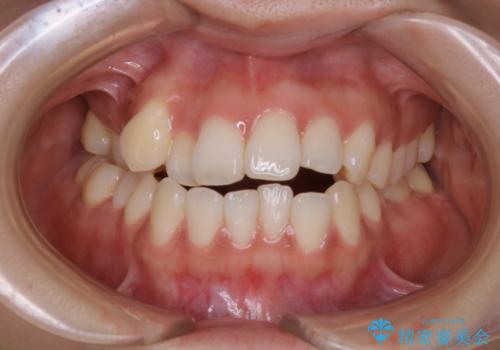

【審美装置】前歯で噛めない!抜歯しないで治したい

MARPEで非抜歯矯正|オープンバイトと八重歯を改善